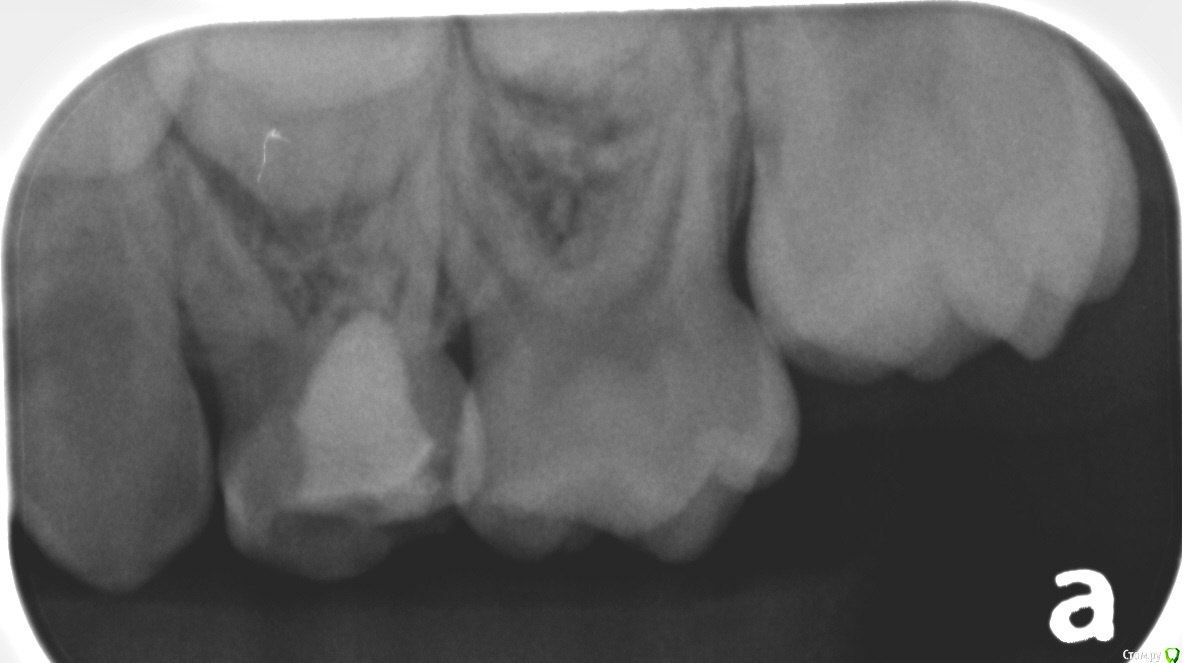

Хотелось бы услышать ваши рекомендации по дальнейшему лечению (ребенку 6 лет).

В первую очередь интересует верхняя левая четверка - в ней разрушилась пломба и часть зуба, сейчас стоит временная полимерная пломба. Есть варант удалить и поставить расширитель, но будет ли хорошей идеей поставить сейчас коронку, или это безнадежно? Сколько она сможет простоять?

Также интересуют остальные потенциальные пломбы/коронки (нам собираются ставить как минимум одну коронку и три пломбы).

Два фото январских и одно от апреля прошлого года (где четверка еще с пломбой).

по поводу верхнего 4 слева - нужен "свежий" снимок . одних только снимков для составления плана лечения не хватит , нужен очный осмотр . если левый верхний 4 не подлежит перелечиванию, то его удалять . справа внизу нужно лечить 4 и 5 , справа вверху 5 .